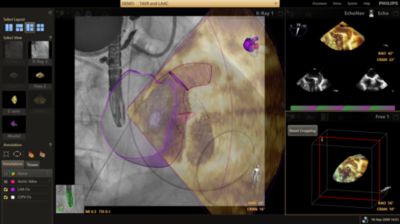

EchoNavigator

Reorient and combine ultrasound and X-ray into a single augmented visualization for guidance and device-tissue relationship assessment. In LAA occlusion EchoNavigator enables the following to elevate confidence and boost efficiency: